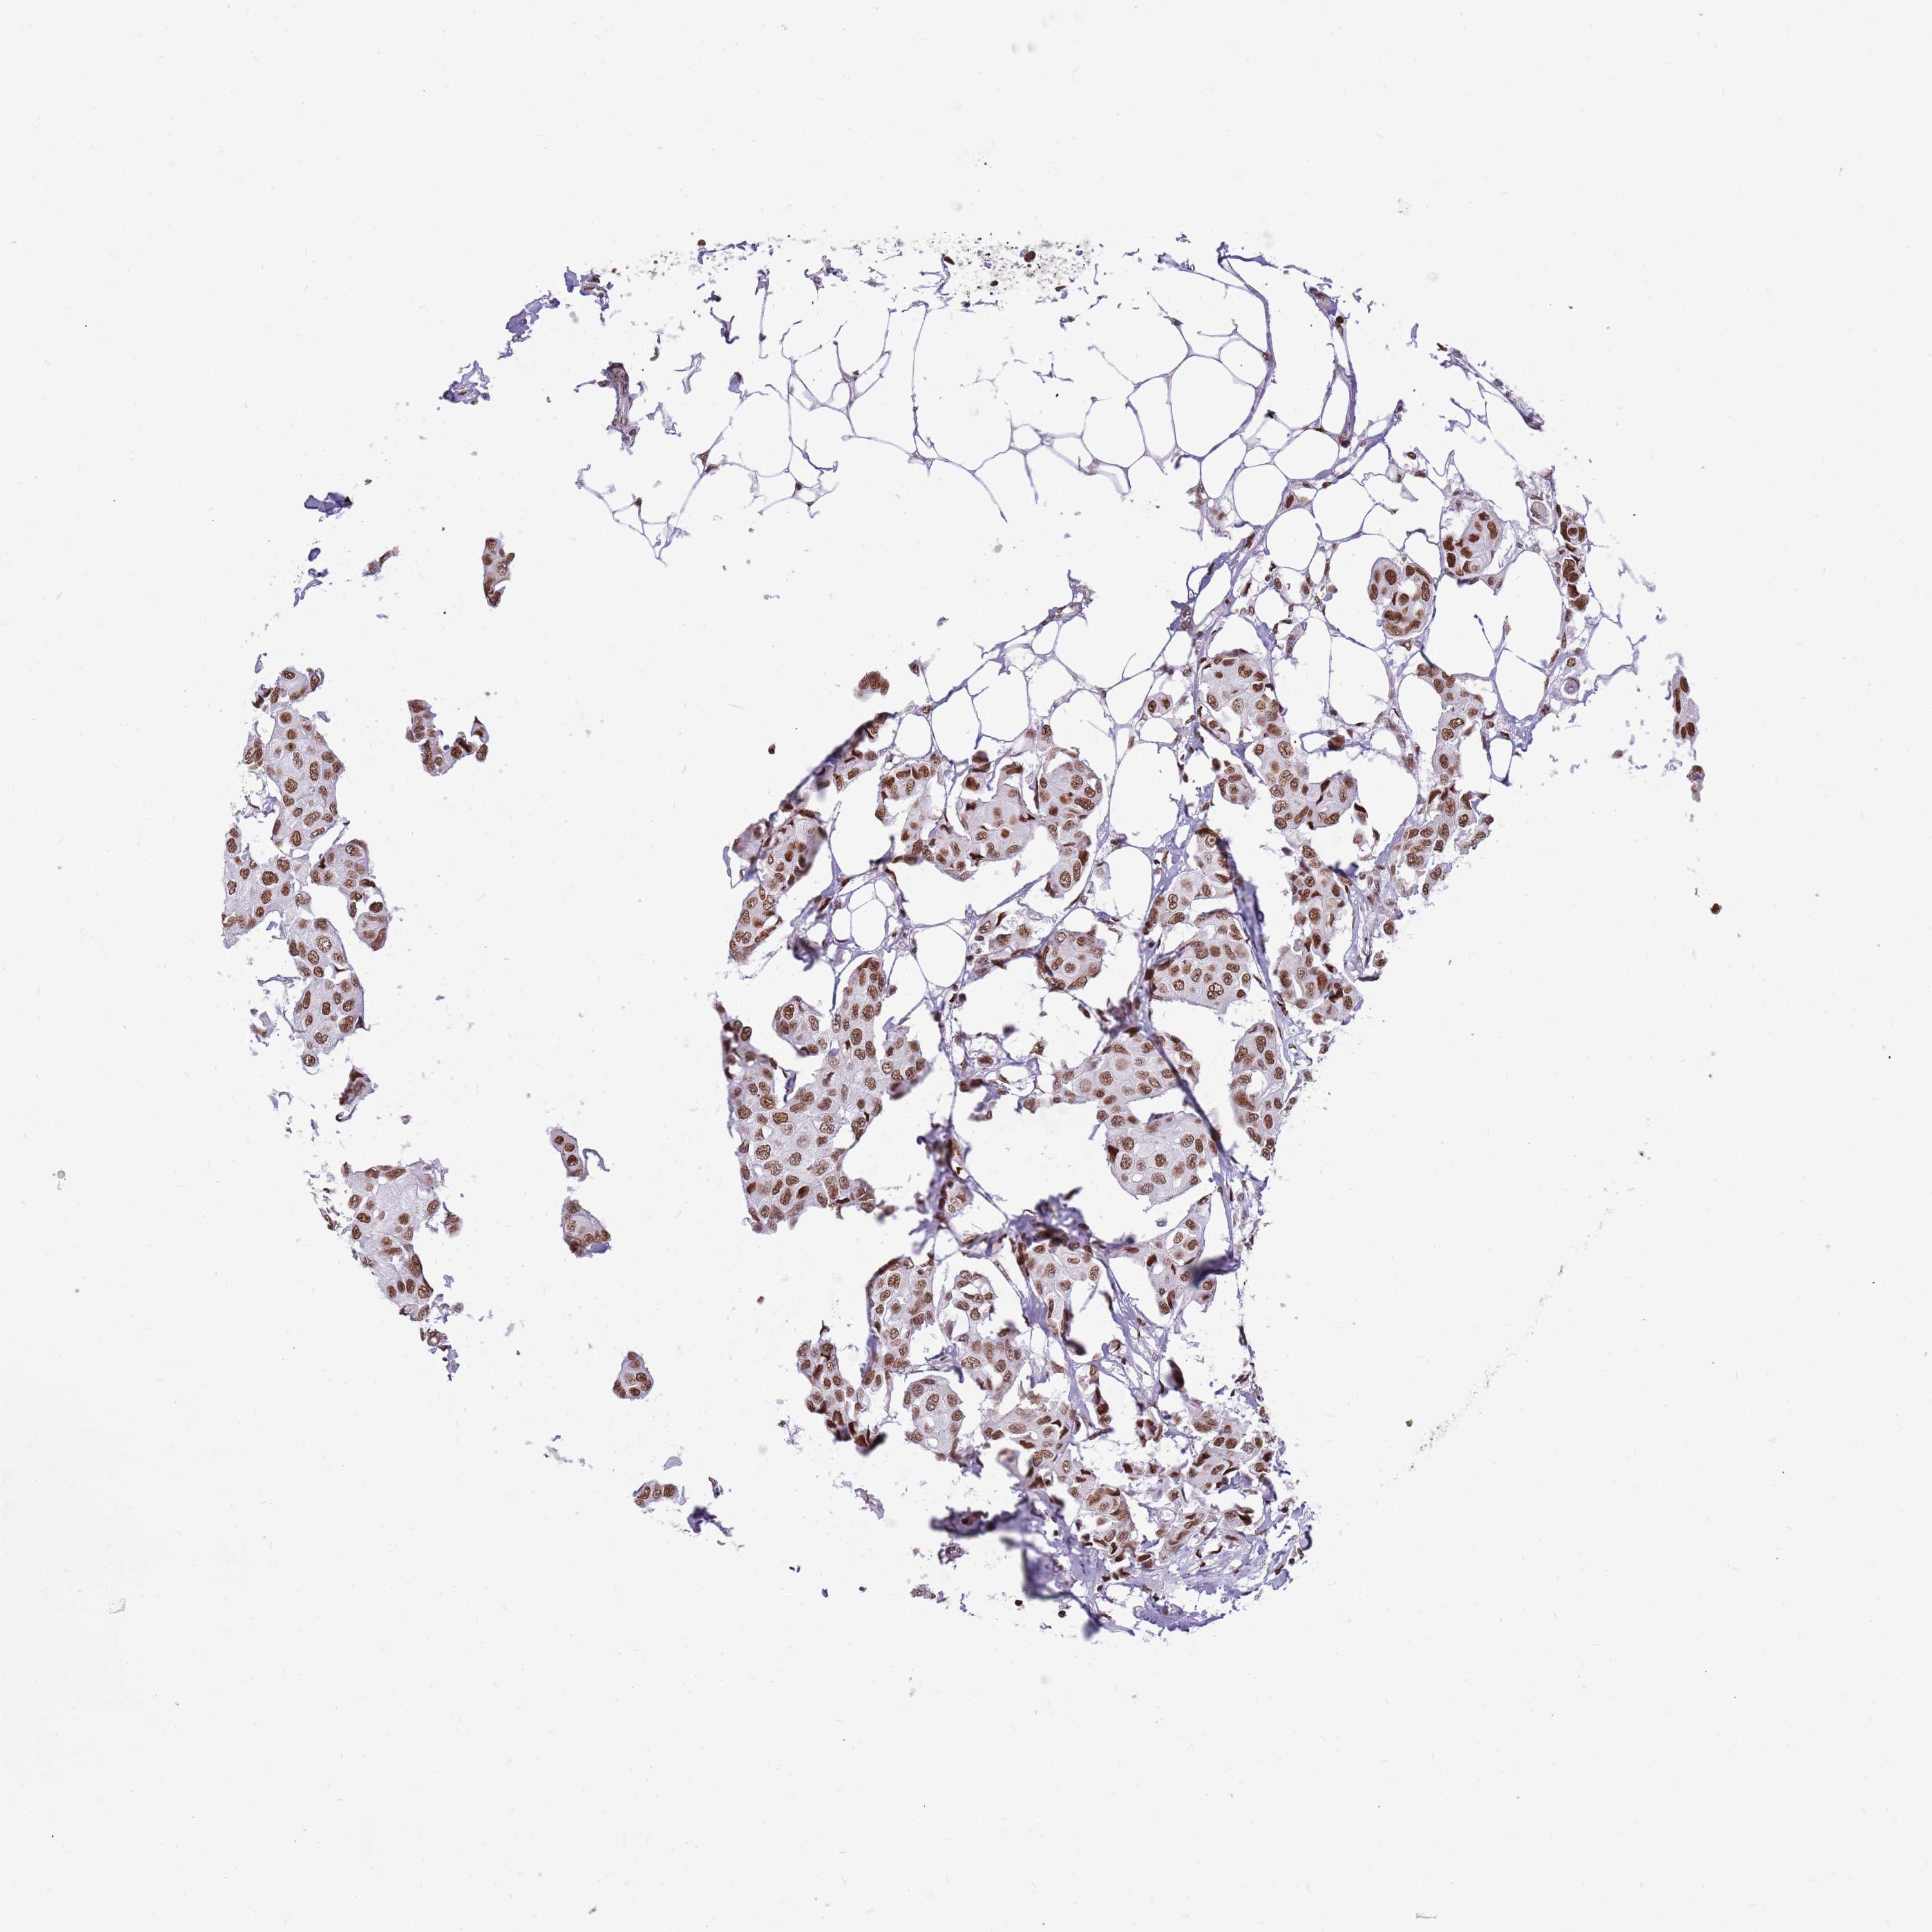

CANCER BREAST CANCER Show tissue menu

BRCA TCGA BRCA VALIDATION PROTEIN EXPRESSION